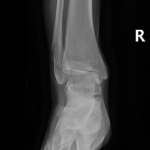

- Ankle Fractures.